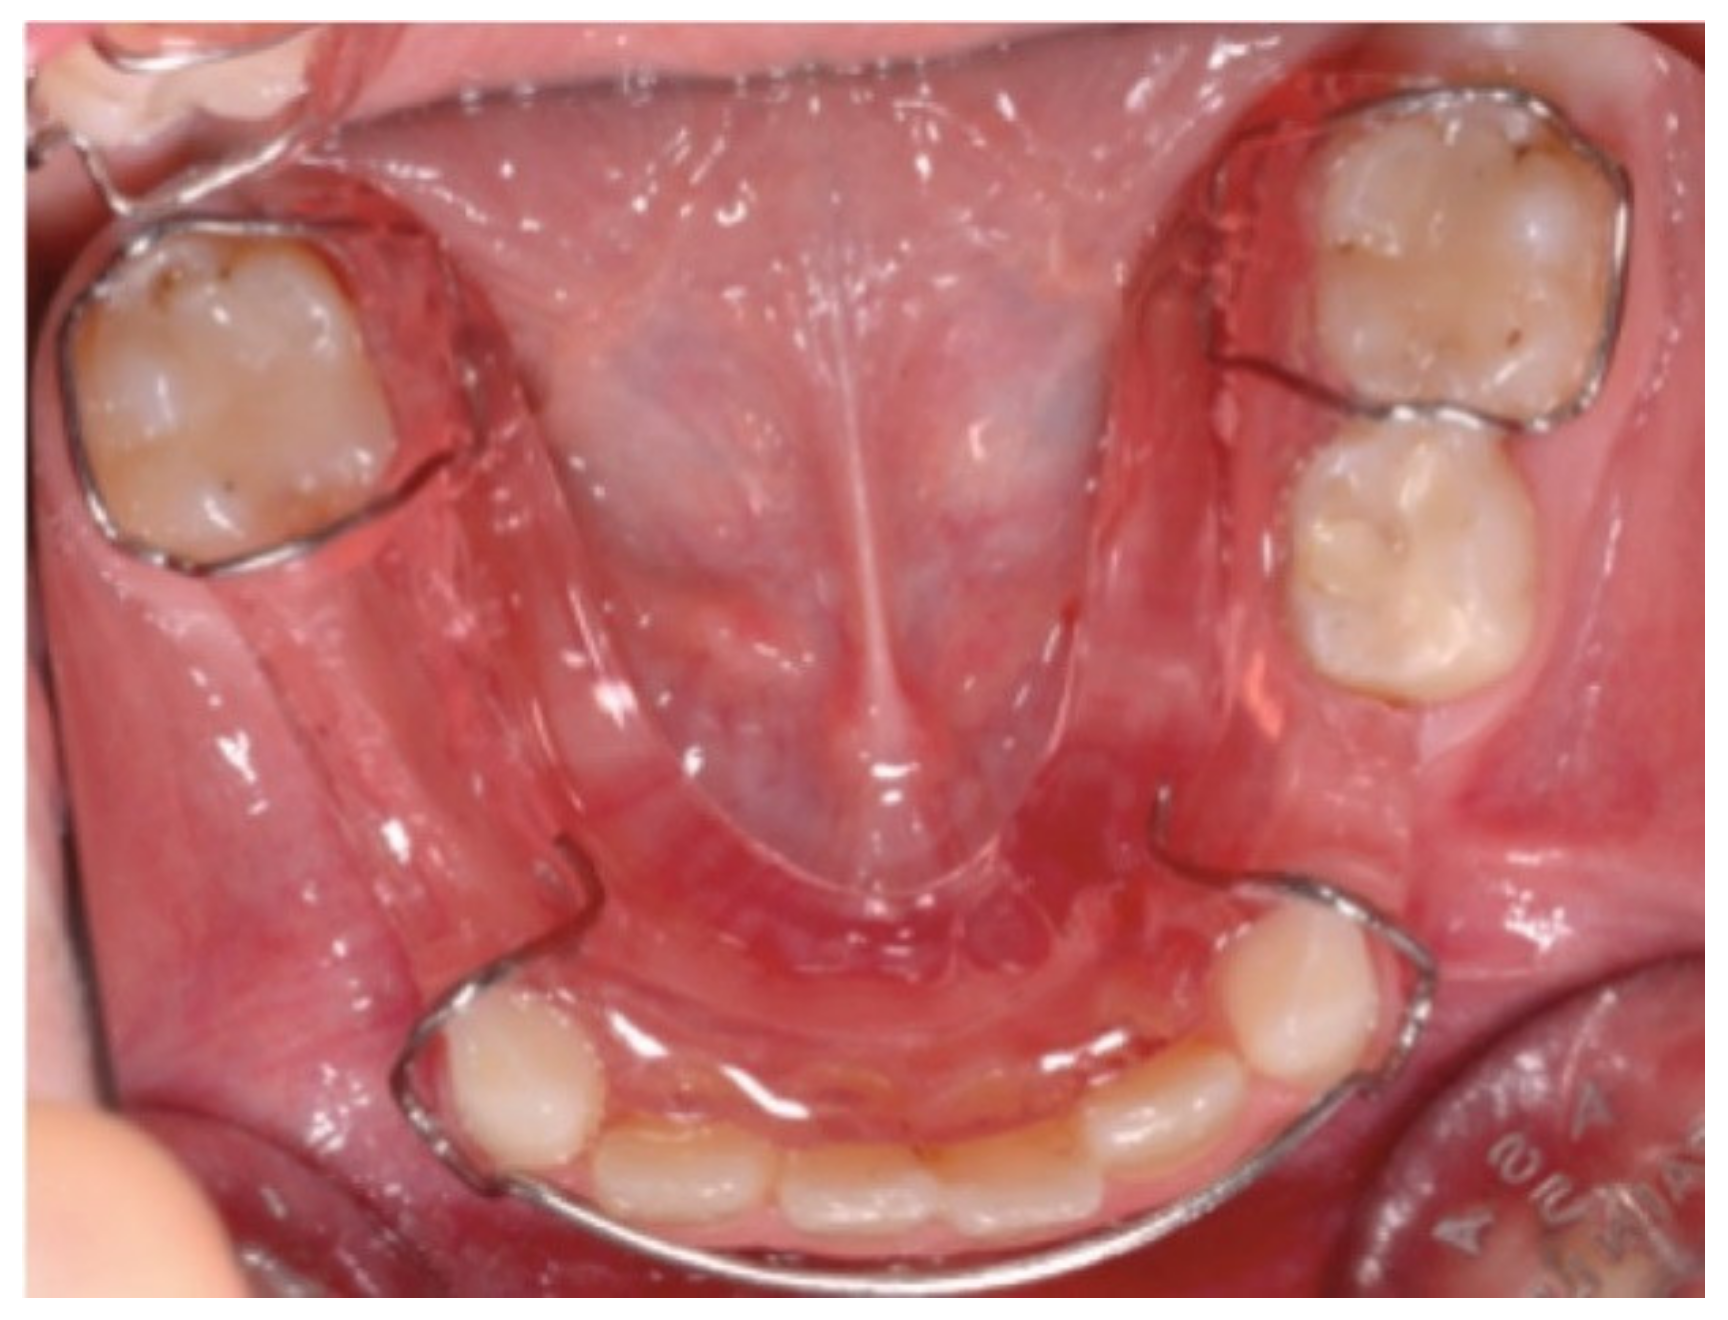

The therapeutic approach to hypodontia is primarily based on a preventive approach which includes the early initiation to oral hygiene maneuvers, the planning of professional oral hygiene sessions at regular intervals, and topical fluor prophylaxis. The main objective is, therefore, the preservation in the arch of the intact deciduous dental element and the maintenance of the dental arch length with the management of the arched space through the use of orthodontic devices with the aim of preventing the mesial migration of the adjacent dental elements (Figure 1).

Figure 1. Example of orthodontic device aimed at maintaining space in the dental arch.